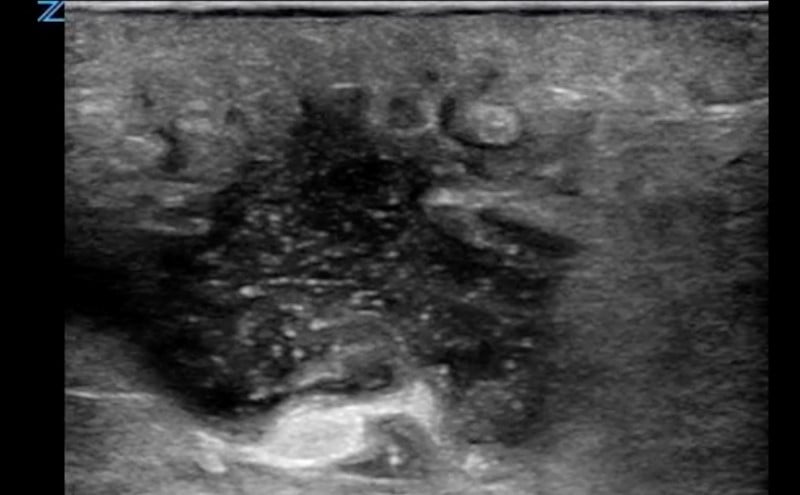

- Figure 2. Abscess containing hyperechoic debris

- On ultrasound, an abscess is a spherical or oblong structure that is largely anechoic or hypoechoic.

- However, as opposed to a simple cyst that will be uniformly anechoic throughout, an abscess will contain hyperechoic debris. This feature can be used to differentiate an abscess from a cyst.

- The walls of the abscess cavity might be distinct and hyperechoic, or they might have a ragged appearance and intermix with the adjacent tissue. Because of the anechoic nature of the abscess, posterior acoustic enhancement might be seen.

- Dynamic scanning, achieved with gentle compression of the probe, might cause the contents of the abscess to swirl, which can be diagnostic of an abscess.